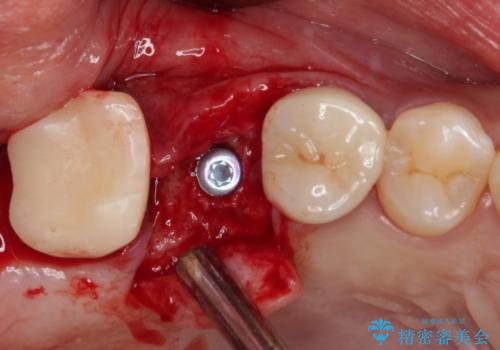

外科処置を回避するためにブリッジ治療を選択されたそうですが、頻繁に脱離するので、欠けた部分のクラウンの作り替えと、欠損部のインプラント治療を行うこととしました。

最後方歯は、クラウンを維持するための高さが不足していたため、インプラント処置の際に歯冠長を延長する手術を併用し、維持力を増すこととしました。

上顎洞までの骨高さが低いケースでしたが、ショートインプラントと骨圧縮機能を持つドリルの使用により、上顎洞底挙上を行うことなく、インプラント治療を行うことができました。